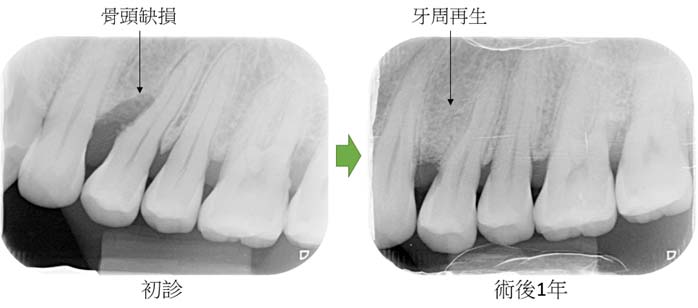

牙周再生手術治療案例2